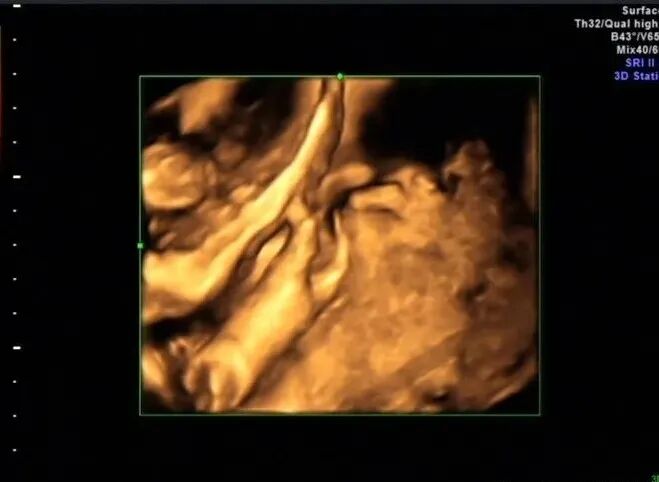

再看脚也不对劲,马上启动三维超声,下图是三维超声表现

手脚都有问题,呈龙虾爪样,非常典型的手裂足裂,胎儿父母没有啥疾病